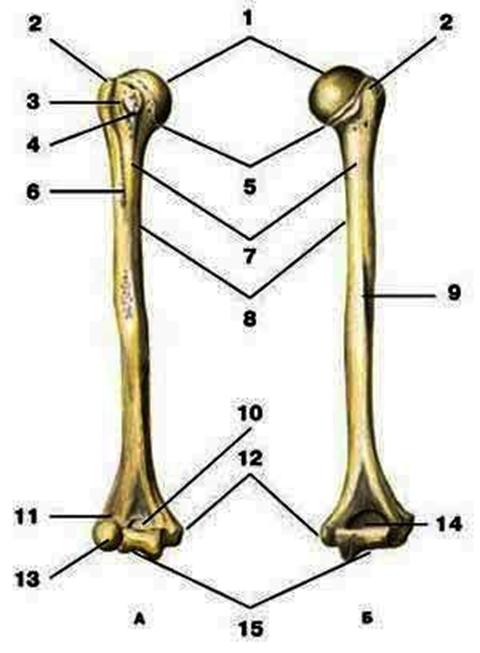

V2:Тема 1.3 Кости верхней конечности и их соединения

S: Цифра 1 обозначает … плечевой кости.

+:сaput

-:t uberculum majus

-:troсhlea

-:capitulum

-:epicondylus lateralis

S: Число 15 обозначает... плечевой кости.

+:trochlea

S: Цифра 5 указывает на...плечевой кости.

+:collum anatomicum

S: Число 10 обозначает... плечевой кости.

+:fossa coronoidea

S: Число 14 указывает на... плечевой кости.

+:fossa olecrani

S: Цифра 9 указывает на... плечевой кости.

+:sulcus nervi radialis

S: Число 12 обозначает... плечевой кости.

+:epicondylus medialis